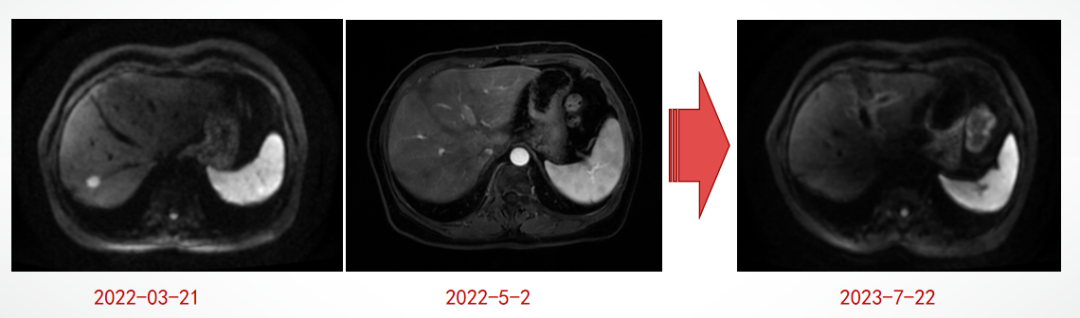

2022-7-30开始内分泌(依西美坦)+HP维持治疗,至2023-09-27。疗效评估:肝转移灶CR,骨转移灶PR。

肝脏转移灶疗效评估:CR

2023-10-12肝转移灶进展:一线治疗PFS 19月。

2023-10-12肝脏MR:肝多发转移瘤化疗后复查,较前片(2023-07-22)病变有增大,肝I段病变为著,累及肝门部结构。